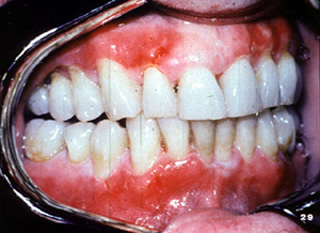

El penfigoide benigno tiene una marcada tendencia a involucrar la encía marginal. La descripción clínica a menudo usada para estas lesiones es "gingivitis descamativa" Debe señalarse que ésta es sólo una descripción clínica y no un diagnóstico definitivo. En la encía  tiene una marcada apariencia eritematosa.

Aquí hay  áreas de ulceración y descamación gingival.